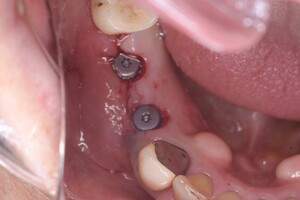

症例写真-1

- Befor

- After

症例写真-2

- 途中経過

| 年齢 | 50代・男性 |

| 主訴 | 右下歯が疼く |

| 治療内容 | ・右下6番インプラント ※1:FGG(遊離歯肉移植術)とは、足りない歯ぐきを上顎から上皮を切り取り移植する外科手術 |

| 治療費 | 合計:902,000円(税込) ■内訳 |

| 治療期間 | 9ヵ月 |

| 治療方針 | 右下の当該歯は歯根破折により保存不可能と診断しました。歯周疾患も伴っていたため抜歯後に骨吸収※1が大きく起こることが予測できました。チタンメッシュ併用骨再生誘導法(GBR※2)を選択しインプラント埋入と同時に行い自然な歯槽骨のラインを再現しました。またGBRを行う際にインプラント辺縁の付着歯肉の減少が起こる為、遊離歯肉移植術(FGG※3)を行い清掃性を考慮した形態に仕上げました。 ■治療方針の解説 治療した右下の歯をレントゲンで撮影したところ根本の部分に黒く写る箇所があり「根尖性慢性周囲炎※1」と診断。また歯周病も進行していました。 ※1 骨吸収・・・歯槽骨という歯を支える骨がなくなっていくこと |

| 担当者所見 | 主訴の右下だけでなく歯茎の腫れ、発赤があり不良補綴や不良充填など他にも治療箇所が多数ありました。プラークコントロールが不良であった為まずはブラッシング指導を行いセルフケアの重要性を理解していただくところからスタートしました。 右下6番の歯はインプラント治療を行なった結果審美的にも機能的にも患者様の満足を得ることができました。骨造成と歯肉移植も行なった為インプラントを支える十分な歯周組織の獲得ができたと思っております。 |